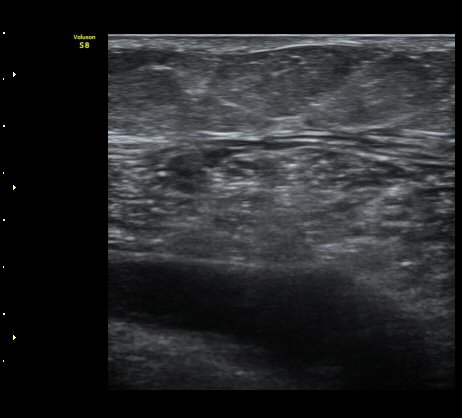

³»Ãøºñº¹±Ù°ú °¡Àڹ̱٠»çÀ̰¡ ¹ú¾îÁö°í ¼ö¾×ÀÌ Àú·ùµÊ.

ÃÊÀ½ÆÄ À¯µµÇÏ ¼ö¾× ÈíÀÎ(÷ºÎ µ¿¿µ»ó) ÈÄ ¾Ð¹ÚºØ´ë °íÁ¤.

³»Ãø ºñº¹±Ù ÆÄ¿Àº ´ë°³ ±Þ¼ºÀ¸·Î ¹ß»ýÇÏ¿© °æÇèÀÌ ÀÖ´Â ÀÇ»ç´Â ºñº¹±ÙÆÄ¿À» ÃßÁ¤ÇÒ ¼ö ÀÖ´Ù.

±×·¯³ª °æ¹ÌÇÑ ÆÄ¿ ÈÄ ¹«¸®ÇÑ ¿îµ¿À¸·Î ÆÄ¿ÀÌ ÁøÇàµÇ´Â °æ¿ì ÅëÁõÀÌ Å©Áö ¾Ê°í º´·Âµµ ¶Ñ·ÈÇÏÁö ¾Ê¾Æ

ºñº¹±Ù ÆÄ¿À» ÃßÁ¤ÇϱⰡ ½±Áö ¾Ê´Ù. ÀÌ·± °æ¿ì¿¡´Â È®Áø¿¡ ÃÊÀ½ÆÄ°Ë»ç°¡ ÇʼöÀûÀÌ´Ù.